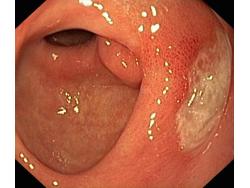

Wrzód trawienny